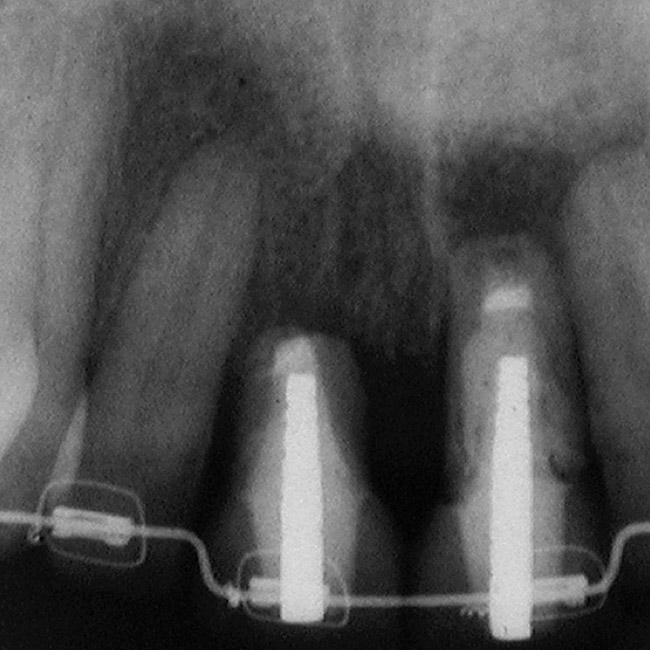

Figure 10  In these adjacent implants placed in the central and lateral positions, note the excellent interproximal bone but minimal interimplant distance.

Figure 10